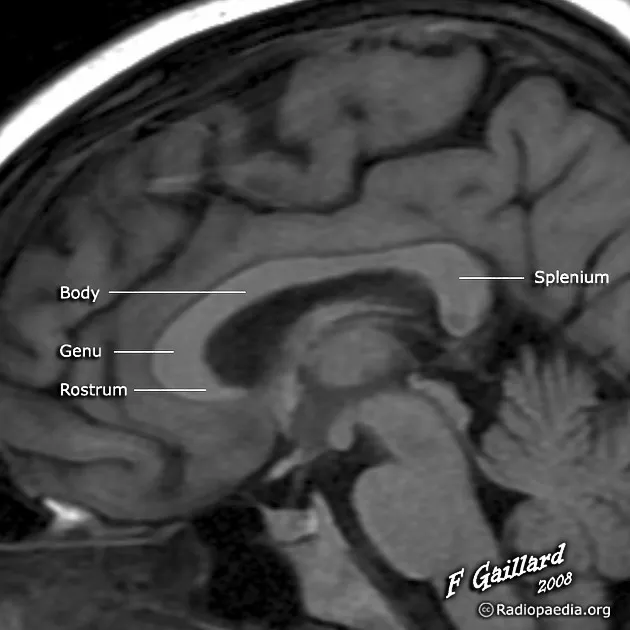

Commissural fibers enable communication between cerebral hemispheres:

Corpus Callosum (200 million fibers)

Anterior Commissure

Posterior Commissure

| Tract | Function | Clinical Significance | Lesion Effects |

|---|---|---|---|

| Corpus Callosum | Interhemispheric transfer | Split-brain syndrome | Disconnection symptoms |